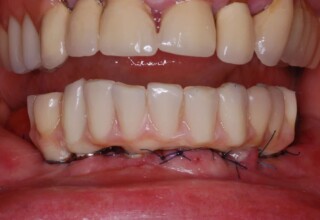

Κάτω γνάθος: εξαγωγές, άμεση τοποθέτηση εμφυτευμάτων και άμεση φόρτιση(την ίδια ημέρα) με προσωρινή γέφυρα

Άνω γνάθος: σταδιακές εξαγωγές, σταδιακή τοποθέτηση εμφυτευμάτων και σταδιακή ενσωμάτωση τους στην προσωρινή γέφυρα ώστε η ασθενής να μην μείνει ούτε μια ημέρα χωρίς αποκατάσταση. Στόχος η συνεχής λειτουργική και αισθητική αποκατάσταση της ασθενούς χωρίς άμεση φόρτιση των εμφυτευμάτων λόγω ανατομικών ιδιαιτεροτήτων.

Χρησιμοποιήθηκαν παλαιές χαμογελαστές φωτογραφίες της ασθενούς γιατί είχε χαθεί τελείως το φυσικό σχήμα των δοντιών εξαιτίας των πολλαπλών προσθετικών προσπαθειών που είχαν γίνει στο παρελθόν. Μεταφέρθηκε στην προσωρινή γέφυρα η σχέση των φυσικών δοντιών μεταξύ τους άλλα και με τα χείλη. Δοκιμάστηκε η φώνηση και η μάσηση με δυο διαφορετικές προσωρινές άνω γέφυρες και εκτιμήθηκε η αισθητική απόδοση τους. Αφού επιτεύχθηκαν σε βαθμό ικανοποιητικό η φώνηση και η αισθητική εμφάνιση της οδοντοφυΐας, η προσωρινή αποκατάσταση χρησιμοποιήθηκε ως οδηγός για την τελική.

Αρχικό

Ενδιάμεσο

Τελικό